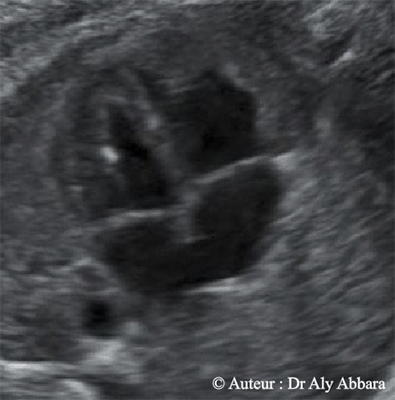

Spot intra-cardiaque - Foyer hyper-échogène au niveau d'un pilier de la valve mitrale

• Images échographiques montrant la présence, dans le ventricule gauche fœtal, un foyer hyperéchogène (spot ou point lumineux - echogenic cardiac focus -ECF ; intracardiac echogenic focus - IEF)

• Le spot intraventriculaire est un foyer ou nodule hyperéchogène (d'une échogénicité égale à celle de l'os) ; il s'agit d'une calcification (minéralisation) du muscle papillaire et d'un pilier valvulaire ; sa taille est habituellement inférieure à 3 millimètre.

• Dans le cas étudié dans cet article, le fœtus est âgé de 28 SA, ne présente aucune d'anomalie significative morphologique, biométrique avec naissance à terme sans trouble de développement.